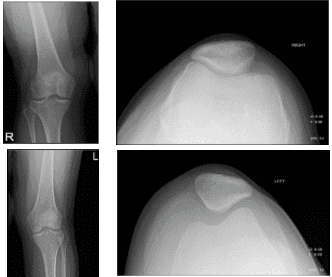

For timing, she reported chronic and nighttime weather. For alleviating factors, ice, and rest. For previous surgery, none. For previous injections, she reportedly helped a little. The patient presented X Ray results that showed small right knee joint effusion. Otherwise unremarkable right knee radiographs.

Knee X-ray complete with patella